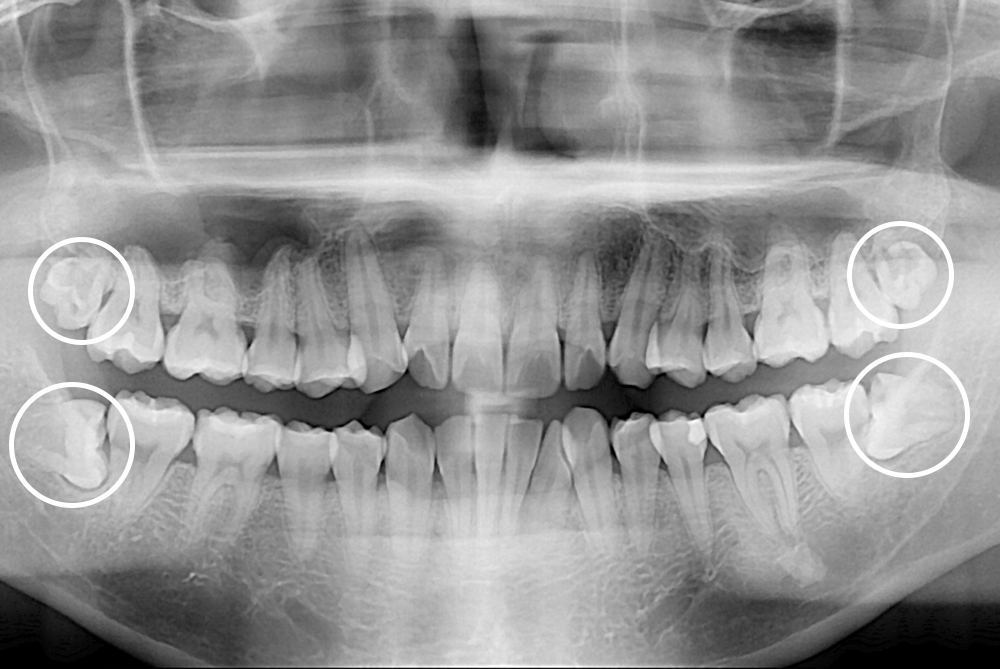

[사랑니] 매복 사랑니 발치

치료후 : 2018-02-03

세종치과는 구강악안면외과학 박사이신 원장님이 발치하는 치과입니다.